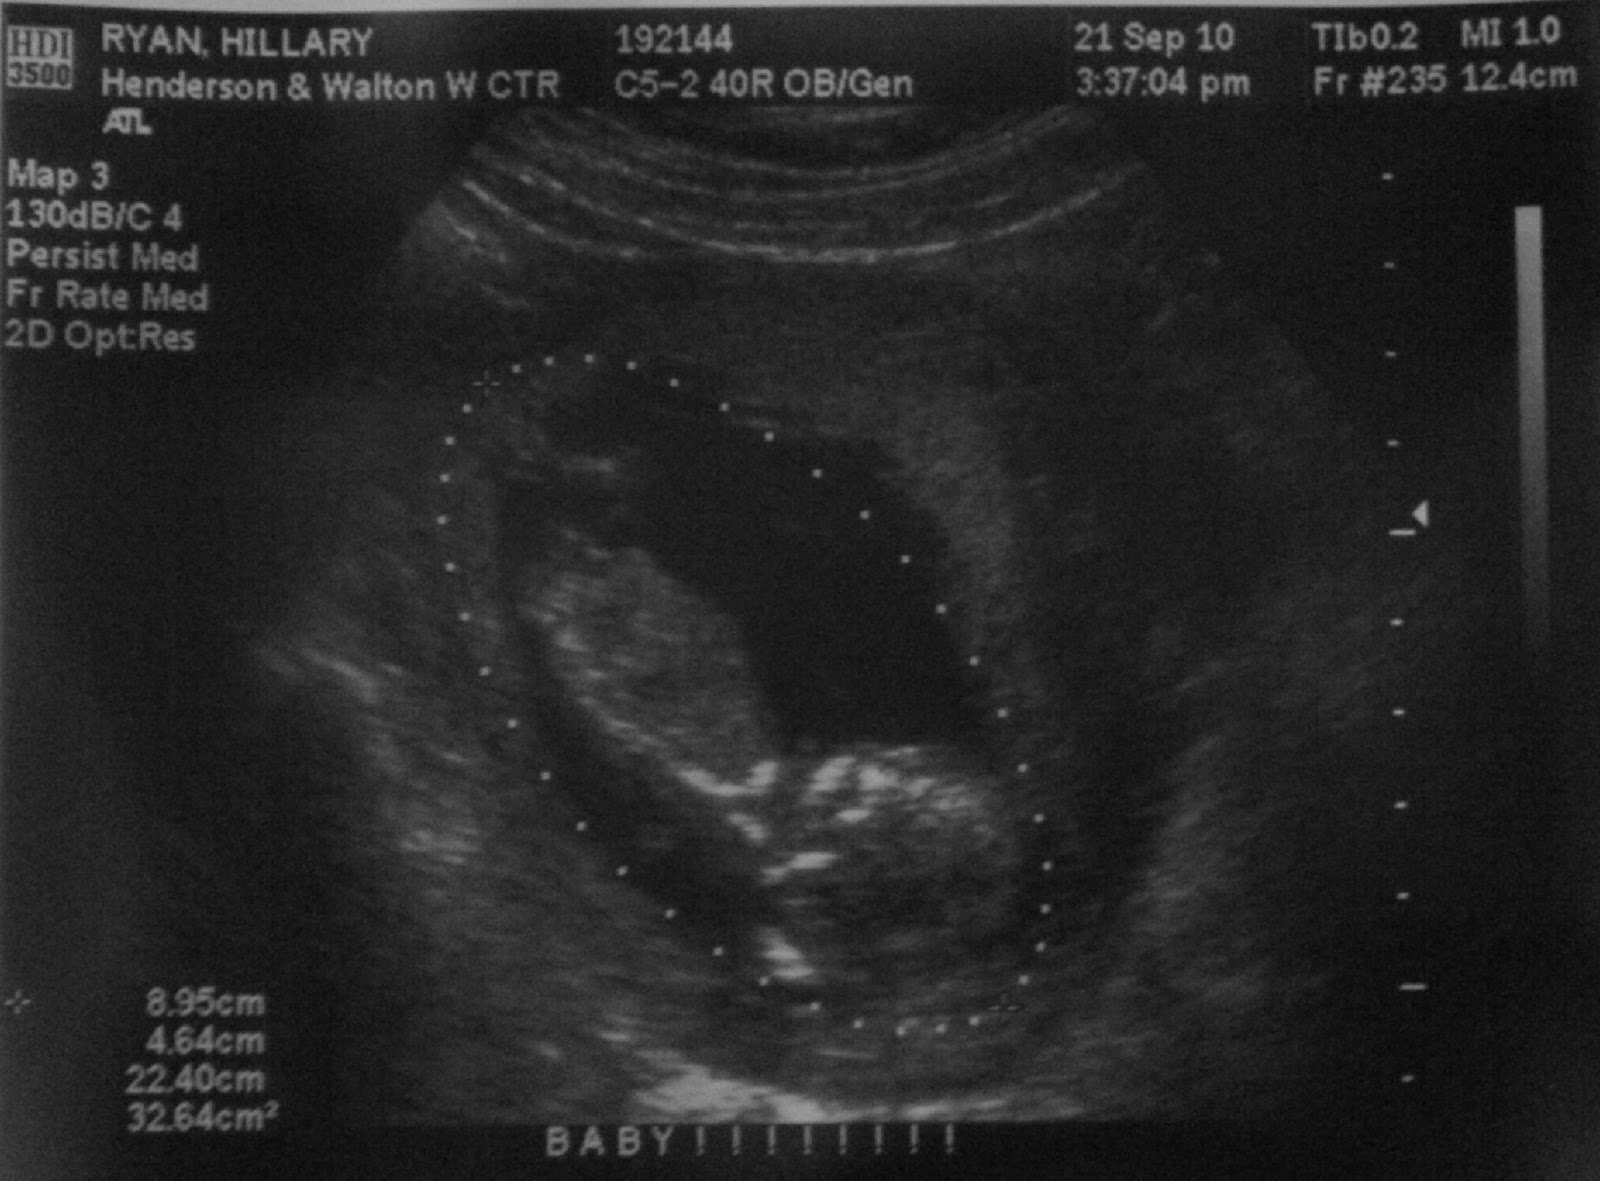

Andrew and I got to see our baby for the first time last week. Have you ever seen a 13 week old fetus stretch its arms and legs? It is by far the coolest thing I have ever witnessed. As I am now nearly in my 15th week, I can't imagine the changes that have already occurred since then. To actually see this human form living, moving, growing inside my body was absolutely surreal. To watch my big, strong husband floored by the sight of his child was mesmerizing. This is life. I hold this life, literally, within me. How amazing is that?

13 weeks, 4 days